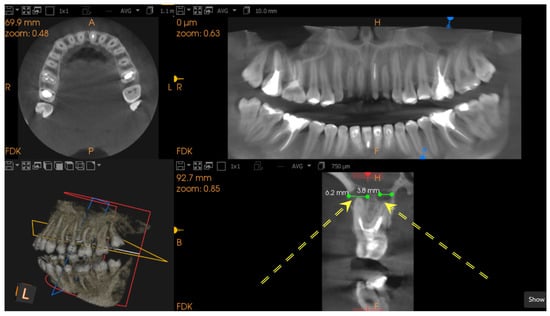

2.3. CBCT Imaging Parameters

- Correct root canal filling, the apical limit of the root canal filling at 0–0.5 mm from the radiological apex;